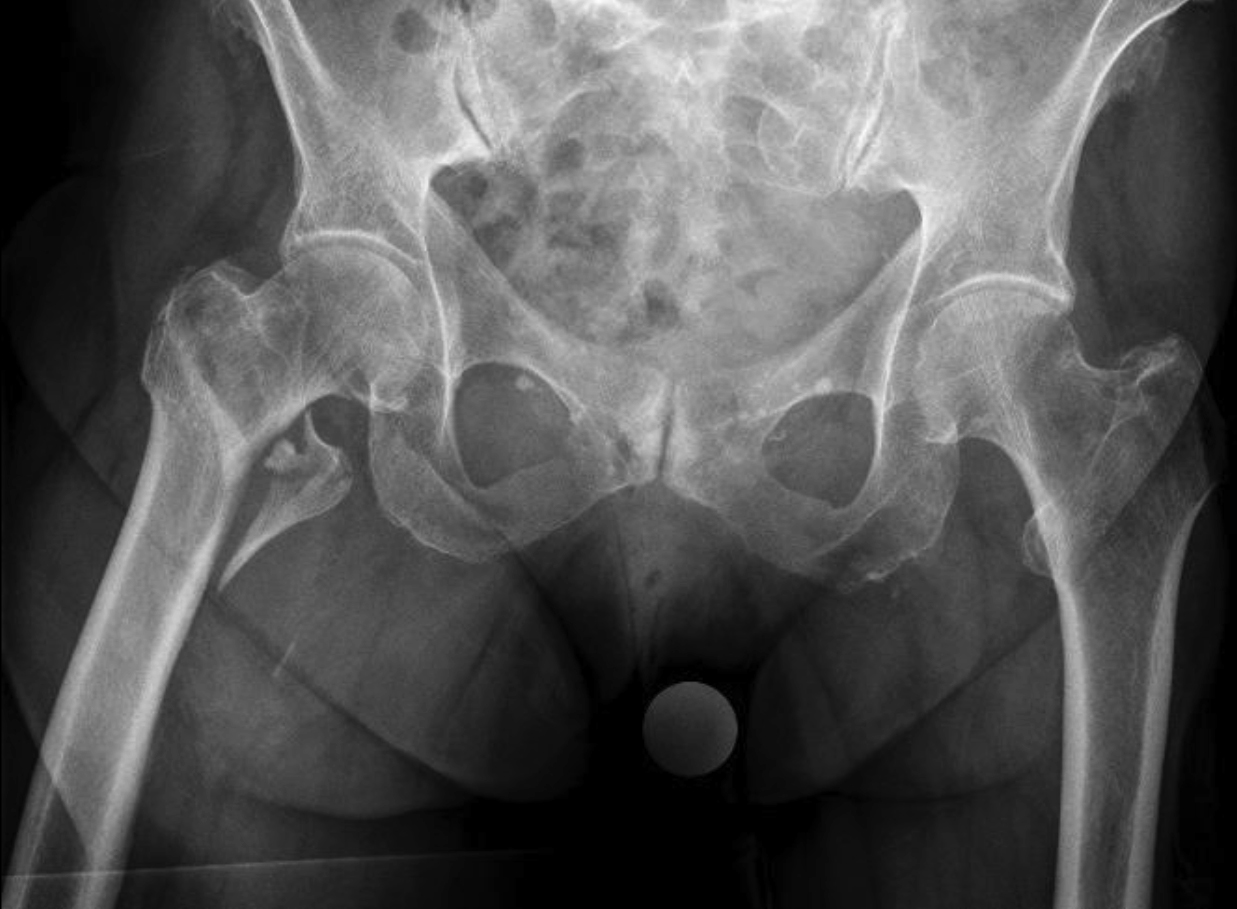

Case 2: Pertrochanteric fracture

A 98-year-old female patient sustained a pertrochanteric fracture of the left proximal femur due to fall in her nursing home (Fig 1). There was significant pain and coxarthritis in the right hip, and hypertension. Surgery was performed within 24 hours. There was an indication for augmentation due to the instability of the fracture. The patient additionally suffered from osteoporosis and dementia.